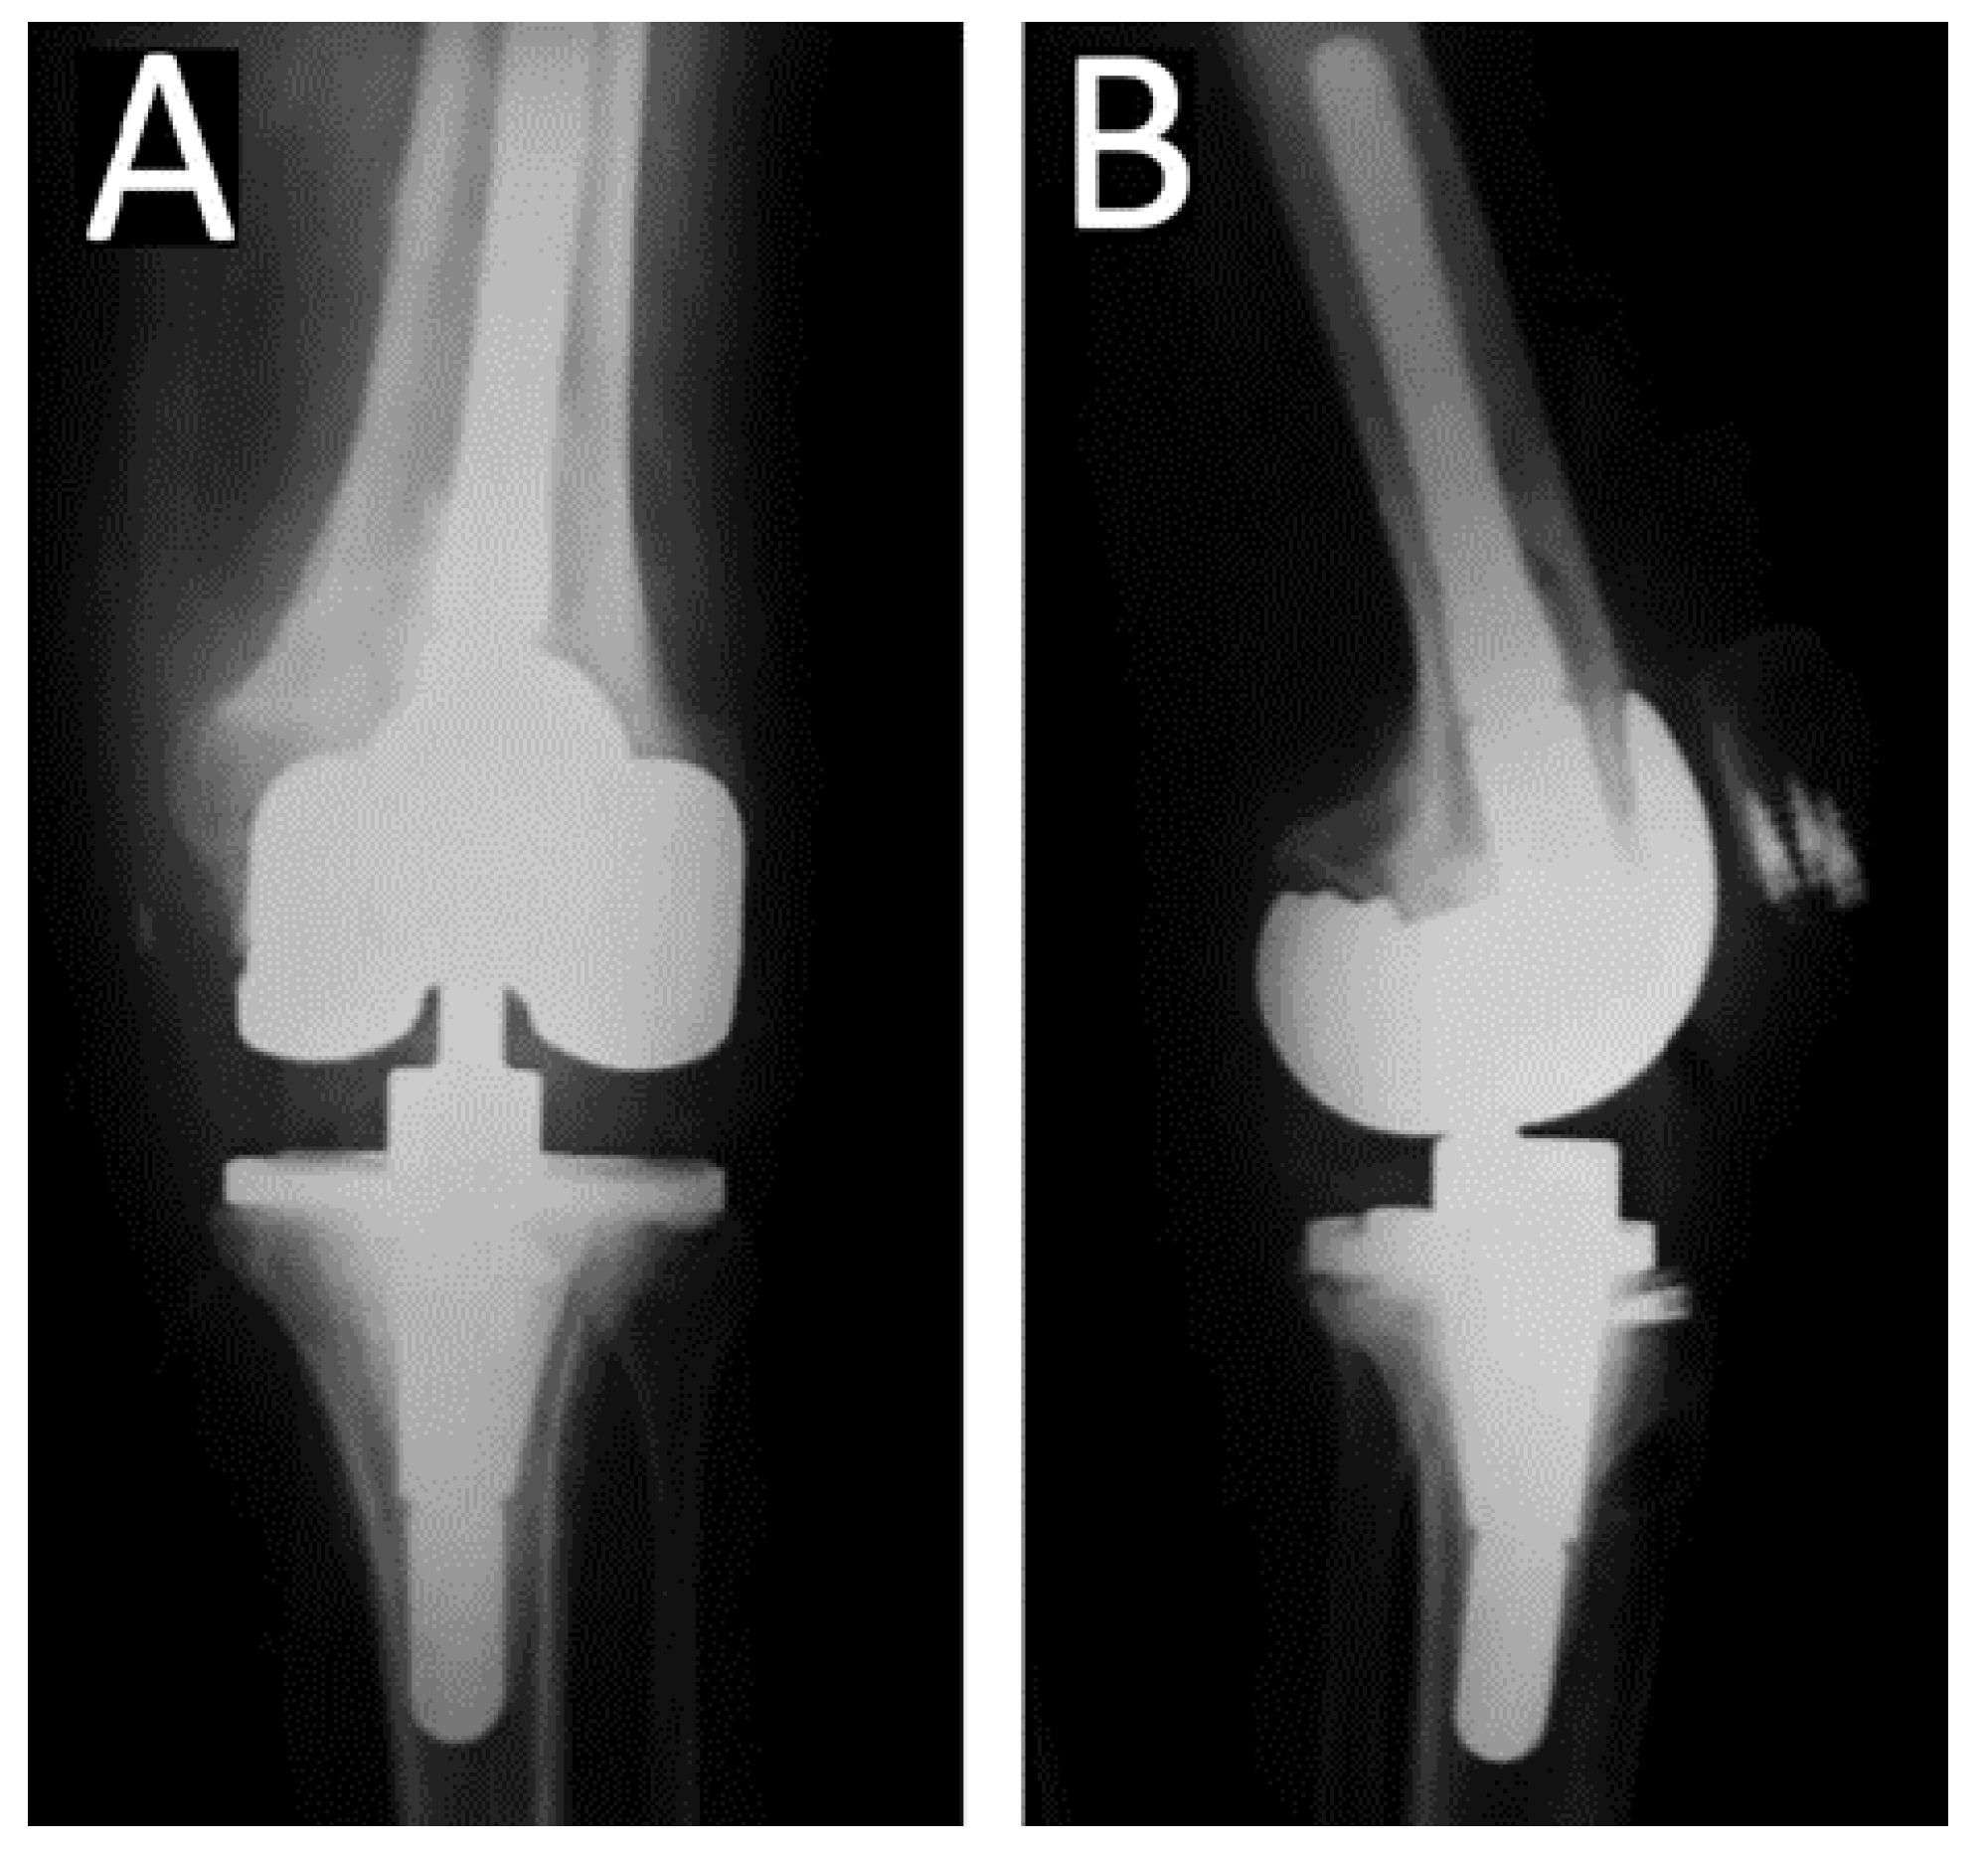

Figure 2.

Due to persistent pain and stiffness the patient underwent revision total knee Arthroplasty (CCK) 6 years postoperatively. Due to intraoperative rupture of the patellar tendon, the patellar tendon was augmented with a semitendonous autograft, combined with a posterior tibialis tendon allograft and a synthetic graft jacket. The patellar tendon was sutured with bone anchors at the distal part of the patella. (A) Anteroposterior and (B) Lateral radiograph of the knee.